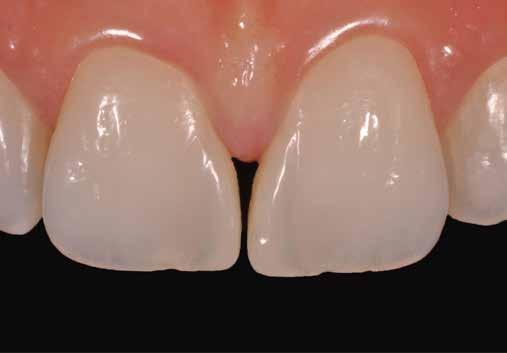

3. eset: Diasztéma zárása, dentin és zománc rétegezéssel az opacitás és a metszőfogtörések korrekciója érdekében (1 óra székben töltött idő)

14.15–16.00 Dr. Jordi Manauta (Olaszország): Szín és forma, a tökéletes anterior kompozitok titkai – a Layers 2 és a Style Italiano módszer Gyakran úgy gondolják, hogy a rendkívül esztétikus fogpótlások elkészítéséhez kifinomult és összetett technikákra van szükség, amelyeket csak néhány kivételesen tehetséges személy képes elsajátítani. Én azonban azt mondom, hogy a tökéletes, nagy sikerarányú fogpótlások elérése valóban mindenki számára lehetséges. Megközelítésünk az egyszerűséget és a logikát hangsúlyozza a racionális színegyeztetés elvégzésében, biztosítva a kiválasztott szín pontos reprodukcióját és a hibákból való tanulást. Napjainkban a megfelelő anyagok kiválasztása, a megfelelő rétegezési technikák alkalmazása és a morfológia kezelése elengedhetetlen ahhoz, hogy pácienseink fogainak legapróbb árnyalatait is utánozzuk, miközben elkerüljük a felesleges kihívásokat, vagy ahogy én szeretem nevezni, a szenvedő fogorvoslást. A 27 év tapasztalatai során felhalmozott tippek és trükkök kincsesbányája áll rendelkezésemre, amelyet szívesen megosztok Önökkel.